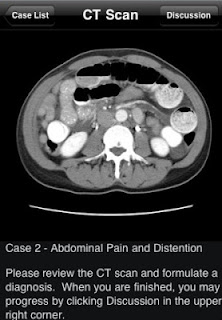

Así que aquí os presento a Daniel Cornfield, radiólogo salido de la Universidad de Yale, y a su Radiology 2.0, disponible para iPhone y iPad, y de forma gratuita, una estupenda aplicación que tiene como misión la presentación de 65 casos clínicos diferentes de urgencia mediante un TAC. Podremos personalizar el menú de tal forma que se pueda elegir conocer o no el diagnóstico antes de ver la imagen (es más recomendable dejarlo oculto y resolverlo viendo los cortes). Una vez vista, se puede pasar a la discusión del caso, donde se resuelve con explicaciones muy claras que poseen links que nos llevan a cortes donde señalan los puntos de interés.

La aplicación, como imagináis, está en inglés. Las imágenes están bien, pero su interfaz está algo limitada (si las comparamos con otras apps radiológicas similares). Pero bueno, no seamos demasiado exigentes, cumple con sus objetivos de proporcionar una buena cantidad de imágenes patológicas con sus comentarios y referencias. Eso sí, ojo que son bastantes y ocupa casi 500 Mb de memoria. Los casos también pueden parecer algo repetitivos, pero es de agradecer que te ofrezcan variedad dentro de un mismo tema.

En conclusión, una buena colección de casos clínicos de urgencias de diagnóstico con TAC, que permite comprobar nuestras habilidades sobre ello, tanto a estudiantes como médicos.